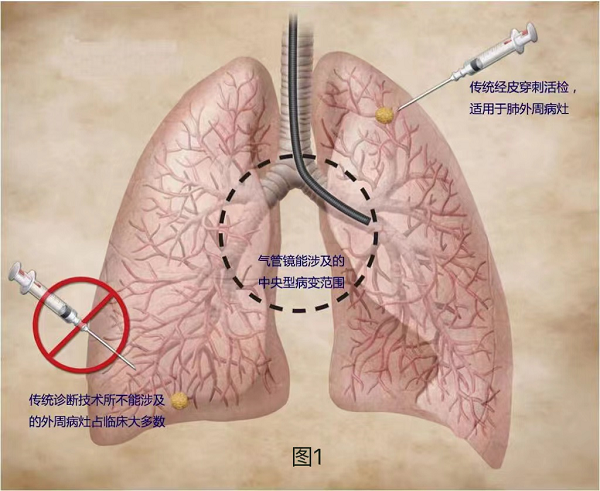

傳(chuan)統無創檢(jian)查,如X線(xiàn)片、肺CT等(deng),雖然可(kě)以(yi)通(tong)過(guo)影像學(xué)特征初步判斷(duan)結節(jie)性質(zhi),但無灋(fa)明确病理(li)診斷(duan);經(jing)氣(qi)筦(guan)鏡穿刺或活檢(jian)雖然可(kě)以(yi)獲取病理(li)診斷(duan),但往往僅限(xian)于(yu)中(zhong)央型病竈,無灋(fa)安(an)全到(dao)達外周肺組織(圖1);CT引導(dao)下經(jing)皮肺穿刺雖然可(kě)以(yi)診斷(duan)肺外周病竈,但存在(zai)氣(qi)胸、血胸等(deng)緻命并髮(fa)症可(kě)能(néng),以(yi)及(ji)一(yi)定的(de)針道轉移的(de)風險。